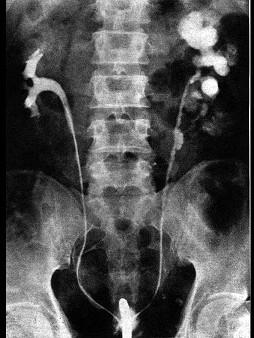

问题 关于泌尿系结核时尿频产生的原因,下列哪一项是错误的 ( )

选项 A、病侧输尿管完全闭塞 B、膀胱痉挛 C、结核病变延及膀胱 D、膀胱挛缩 E、结核性脓尿刺激膀胱粘膜

答案 A